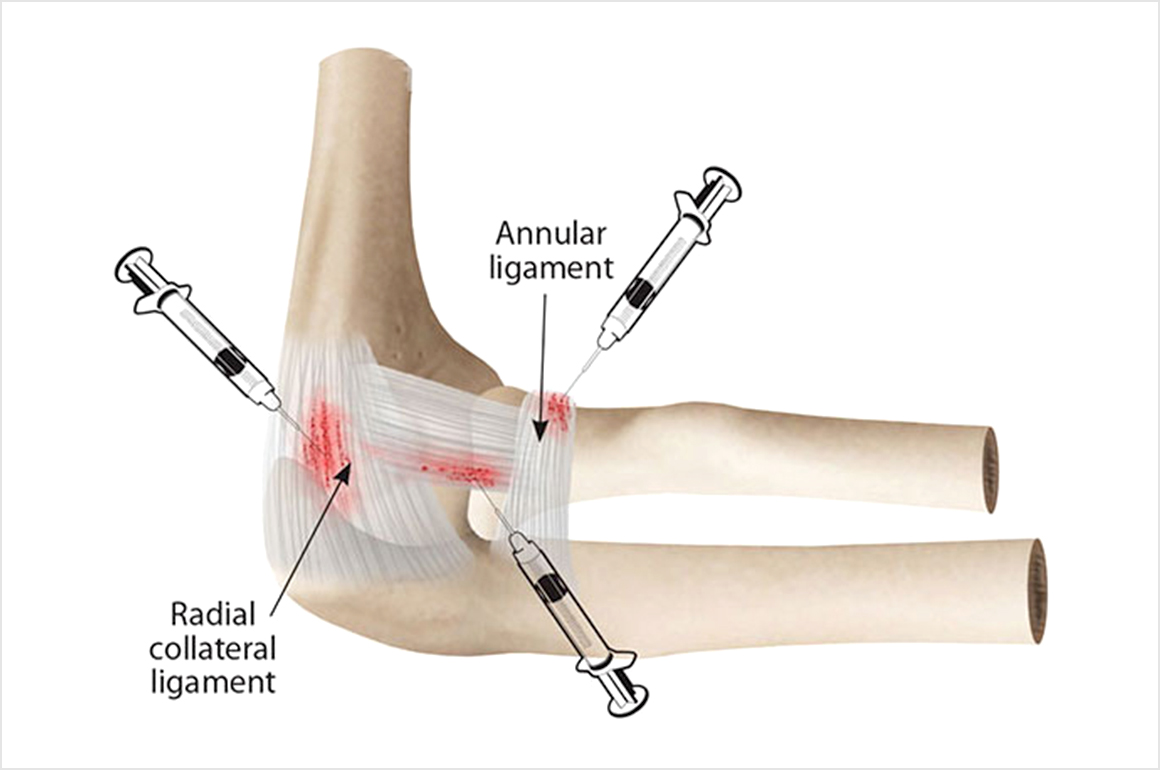

프롤로 주사 (인대강화주사)

치료 대상  :  인대손상, 관절통, 건초염 등

인대나 힘줄 부위에 조직의 자연치유기전을 가속화시키는 증식제를 주사해 인대 조직을 두껍께 강화시켜주는 일명 프롤로치료 또는 증식치료라고도 불리우는 주사입니다.

적당한 염증 반응을 일으켜 인대와 힘줄과 같은 연부조직이 치유되고 새롭게 생성되도록 하여 약적인 구조를 강화시킵니다.

적당한 주기로 주사를 반복하여 손상부위의 안정성을 점진적으로 재건해줍니다.

초음파 영상을 보며 원하는 부위에 정확히 약물을 주입하며 팔꿈치, 손목, 발목 등 많이 사용하고 손상되기 쉬운 다양한 관절에 효과가 있습니다.